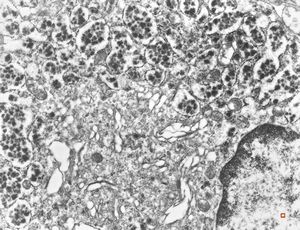

normal seromucinous salivary gland